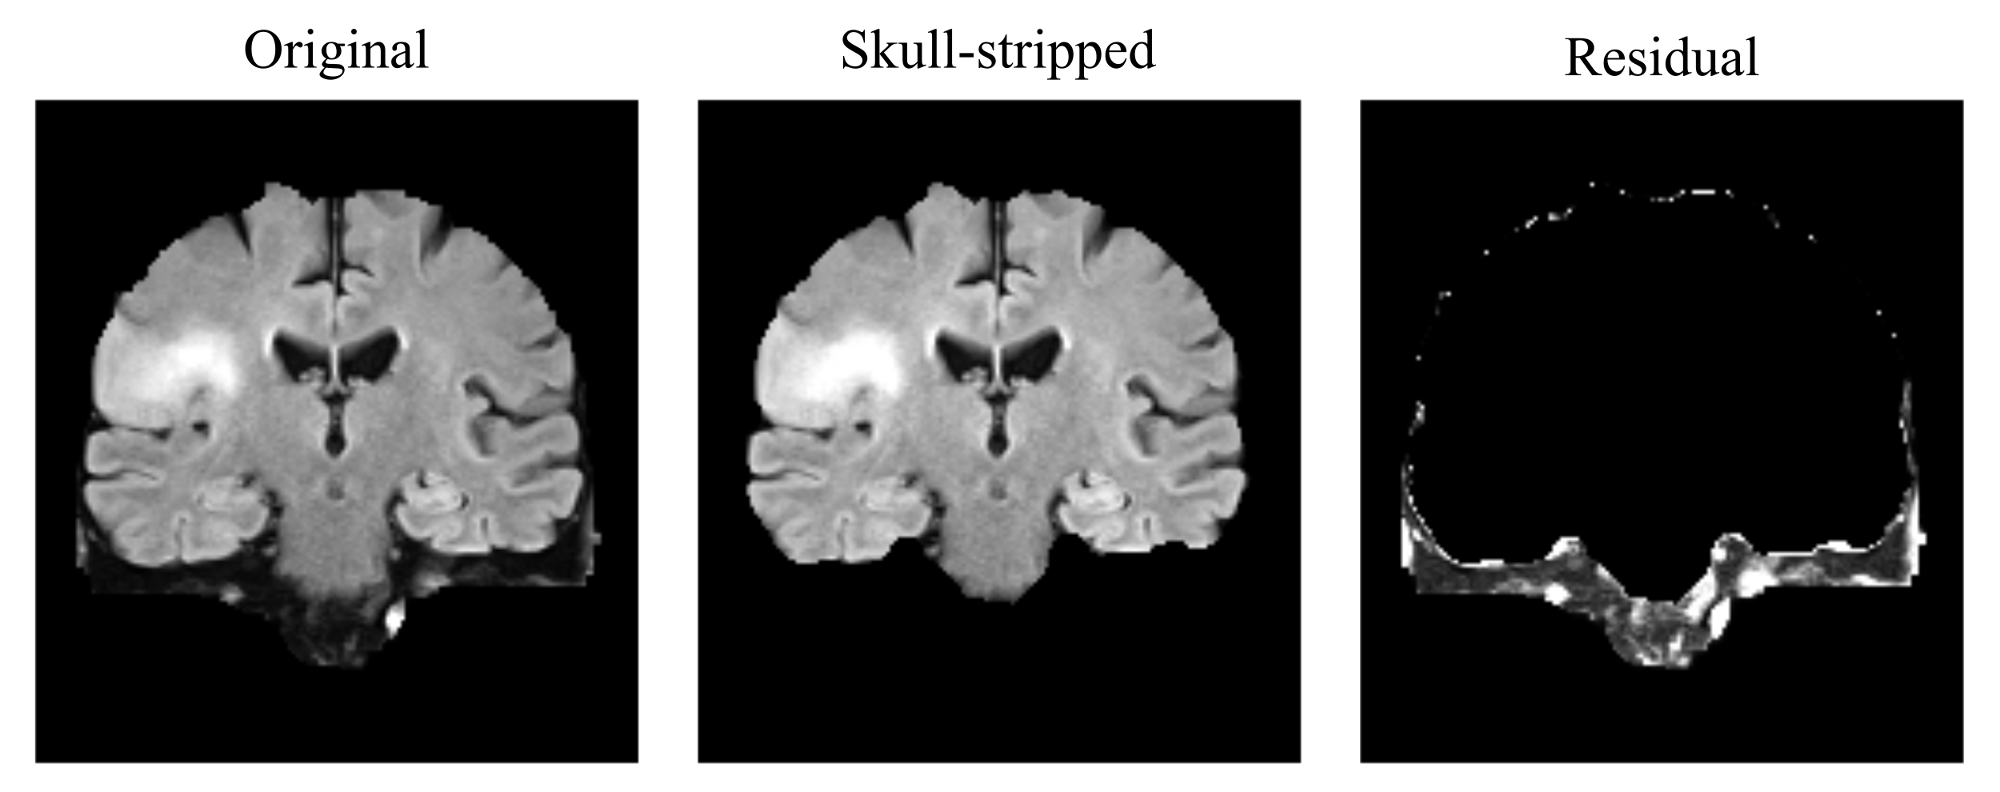

First, in order to verify that unsupervised learning methods are reliable to extract MRI patterns to describe the heterogeneity of a lesion, a comparison among several structured and non-structured unsupervised learning methods was conducted for the task of high grade glioma segmentation. Additionally a generic postprocessing stage was also developed to automatically map each label of an unsupervised segmentation to a healthy or pathological tissue of the brain.

Comparative study of unsupervised learning algorithms for glioblastoma segmentation

In this study, a comparison of unsupervised learning algorithms, including structured and non-structured methods was performed for the task of high grade glioma segmentation. The study describes the statistical model underlying each algorithm and also proposes a general post-processing stage to identify which classes of an unsupervised segmentation correspond to pathological or healthy tissues. An independent evaluation of the performance of the unsupervised learning algorithms was carried out in a public real dataset, which demonstrated the capability of unsupervised learning to extract relevant knowledge from MRI data. This work was published in the journal contribution P1 (Juan-Albarracín et al, 2015b) and presented in the conference P2 (Juan-Albarracín et al, 2015a).